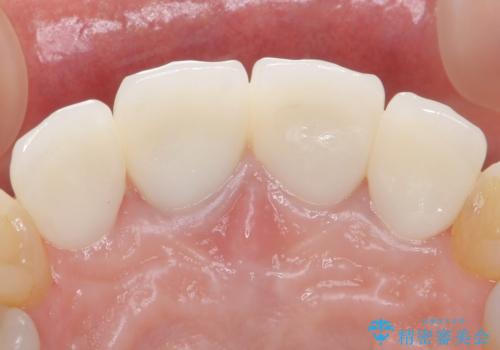

自然な前歯にしたい ジルコニアクラウンでの修復

歯ぐきの炎症を抑えつつ、被せ物と歯との境目がわからなくなるよう被せ物を装着しました。

審美性が大変改善されたことで患者様にもご満足いただけました。